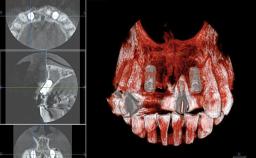

In November 2010, a 44-year-old woman presented to the Harvard School of Dental Medicine seeking options to replace her failing six-unit conventional prosthesis. Having served for approximately 10 years, the fixed partial denture had repeatedly needed recementation after chronic dislodgement over the past few months. Following these episodes, the patient requested further evaluation of her current prosthesis and showed interest in exploring other options for a fixed solution. The patient was in good overall health, presenting with no systemic contraindications to implant therapy or any history of allergies; she did not smoke and was on no medications. Being a well-motivated individual, she regularly saw her general dental practitioner and effectively complied with oral hygiene requirements.

Bone Volume | Deficient horizontally, allowing simultaneous augumentation |